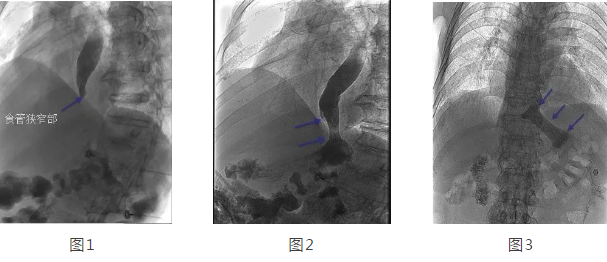

在韓國宏教授的帶領(lǐng)下,專家團(tuán)隊(duì)經(jīng)多方面評估后,決定在DSA下為劉大爺行食管造影 食管支架置入術(shù)。術(shù)中透視可見食管中上段擴(kuò)張明顯,食管下端賁門口明顯狹窄,造影劑淤積,呈線性緩慢進(jìn)入胃腔(見圖1),經(jīng)過準(zhǔn)確定位后,釋放食管支架,再次造影可見造影劑經(jīng)支架順利進(jìn)入胃腔(見圖2)。2天后再次造影見食管支架完全打開,位置正常,造影劑可順利通過支架(見圖3)。